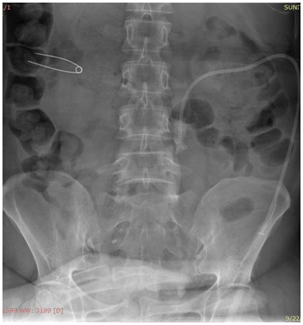

Patient was placed in the prone position, cleaning and draping of the region was done and skin infiltrated with 1% lignocaine. Following an incision with surgical blade (no 11) puncture needle (18/21 gauge) was introduced into the dilated pelvicalyceal system (PCS) under real time USG guidance using a trans abdominal convex probe of 4-9MHz Figure 1. Urine/pus was aspirated on PCS access for culture and sensitivity.

Figure 1 Longitudinal sonogram showing the entire course of the needle(arrow) traversing renal cortex with the tip in the dilated PCS

Precise point of entry was confirmed by a performing a nephrostogram and once the access into target calyx was confirmed the needle was exchanged over 0.035 Terumo guide wire. The tract was serially dilated, catheter introduced and guide removed after confirming correct placement of catheter tip. The nephrostomy tube was secured and urobag attached. Post procedure nephrostogram was performed Figure 2.

Figure 2a Radiograph showing the puncture needle in the dilated opacified PCS.

Figure 2b Radiograph showing the guidewire in the opacified PCS and the ureter with the needle in the PCS.

Figure 2c Radiograph showing dilator over the guidewire inside the opacified PCS.

Figure 2d Radiograph showing malecot’s catheter in the opacified PCS.